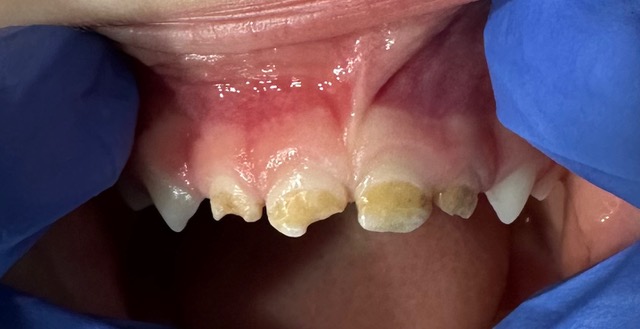

When a cavity is too large for a filling, a pediatric crown provides the strength and protection a tooth needs to stay healthy.

At Luce Tooth, we offer both stainless steel and beautiful tooth-colored zirconia crowns, giving each family the option that fits their child’s needs and smile.